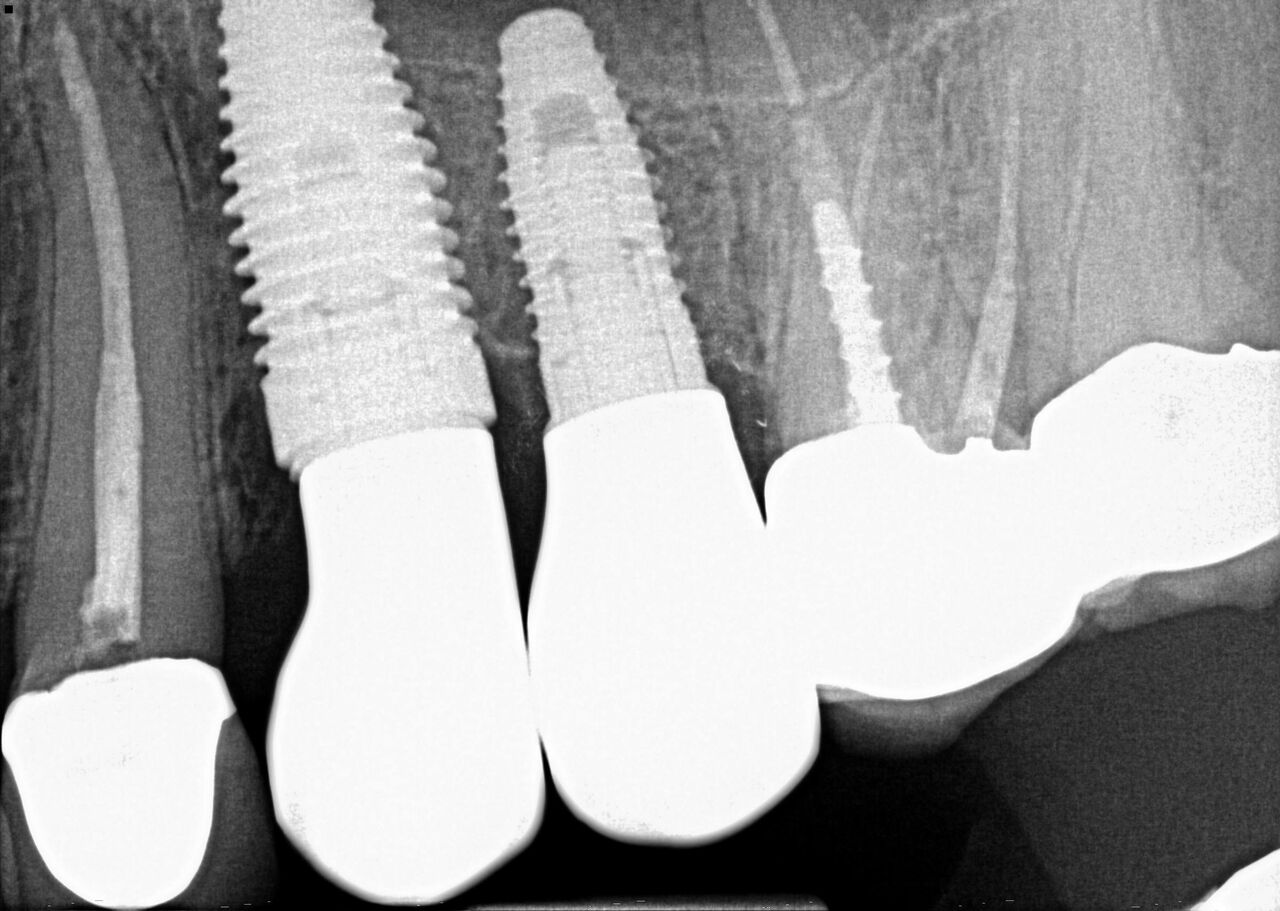

(24.) Radiograph of postoperative individual crowns on Nos. 6 through 10.

Figure 24

(25.) Radiograph of postoperative individual crowns on Nos. 6 through 10.

Figure 25